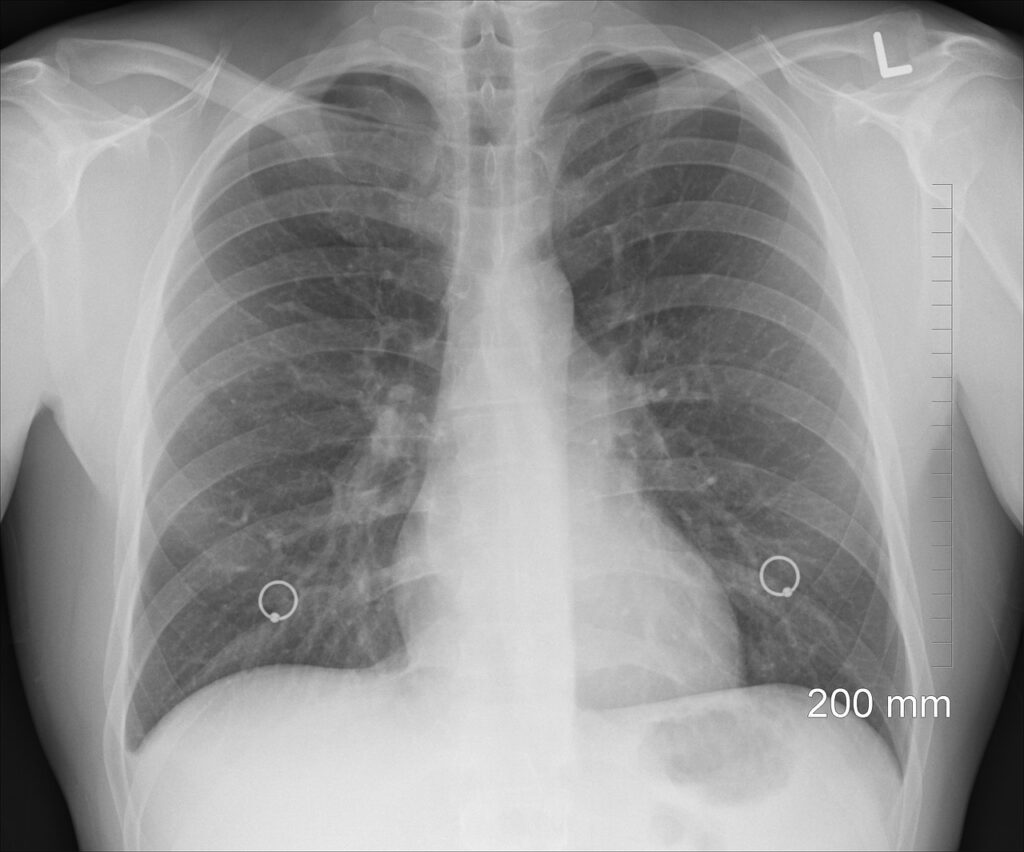

- Alveolar Lungs: Millions of alveoli for gas exchange.